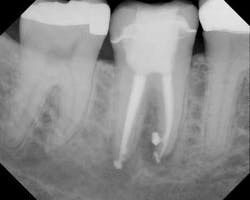

Preop

Postop